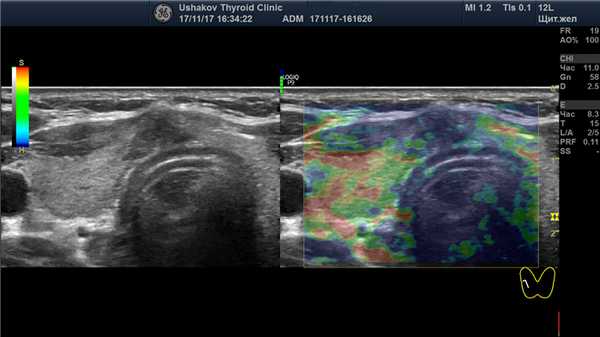

| Рисунок 1. В правой части перешейка щитовидной железы узел с признаками рака: 1) неправильная форма, вытянут не вдоль, а поперёк перешейка, 2) содержит значительно гипоэхогенную ткань, 3) граница узла в некоторых участках прерывистая. Класс по TI-RADS соответствует 4С. | Рисунок 2. Этот же узел в режиме ЭДК. Кровоток узла значительной интенсивности с признаками неупорядоченности распределения сосудов. |

Рисунок 3. Этот же узел в режиме компрессионной эластографии. Значительно увеличена жесткость узловой ткани ― признак плотного расположения клеток в ткани узла (свойственно злокачественности).